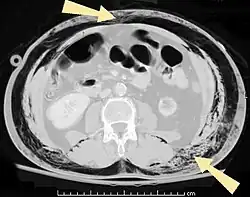

Ar subcutâneo (flechas) pode ser visto como áreas escuras nesta tomografia compudatorizada da pélvis.